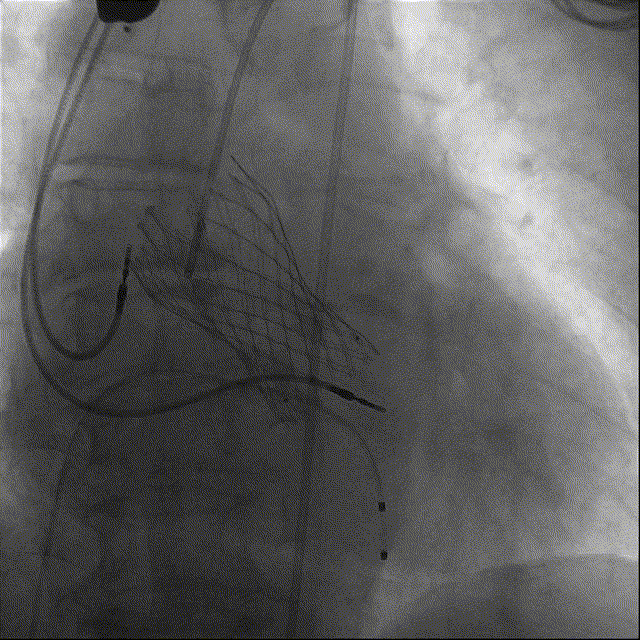

瓣膜释放后主动脉瓣根部造影提示瓣膜位置良好、冠脉显影正常。

在团队配合默契下,手术顺利完成,术后即刻造影及超声检查提示:瓣膜位置良好,冠脉显影正常,存在少量瓣周漏,术后压差2mmHg(术前53mmHg),二尖瓣返流明显减轻。术中血流动力学稳定,术后患者即刻拔除气管插管。术中及术后未出现相关并发症,手术圆满完成。